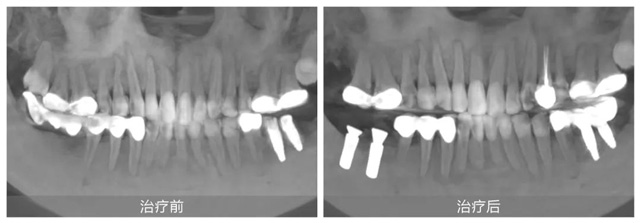

果然,徐會醫生不負所托輕松完成了劉女士下頜左側的牙冠修復。并對其他牙齒問題提出了一套綜合治療方案:先拆除不良修復體,拔除下頜右側的傾斜智齒,然后在缺牙處植入兩顆種植牙,并對前磨牙實施根管治療。這一方案更加微創,也更加經濟和高效。